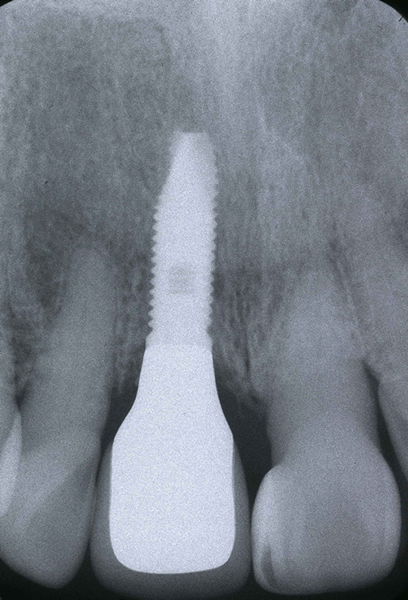

歯科治療では、インプラント治療に限らず見えない部位を診断するために上図のようなレントゲン写真を撮影する必要があります。

当院では、確実な現像・定着・水洗・乾燥・保存処置を行うことで考えられる最高のレントゲン写真の質を確保しています。

しかしながら、立体的な被写体(歯、顎骨など)に対してフィルムやパソコン上に写っているものはあくまで平面的な(2次元的な)像で実物とは異なります。

私たち歯科医師は知識と経験から頭の中で得られた画像を立体的にふくらませているというのが一般的なのです。

そこには像のゆがみや、実際の治療の段階で想定外の口腔内の状態であることが多くあるのも事実です。

CT 撮影をすることによってインプラントを埋入する骨の状態(厚み、高さ、欠損状態、密度)や神経・血管の位置をあらかじめ正確に把握でき、安全に速いインプラント治療が可能となりました。